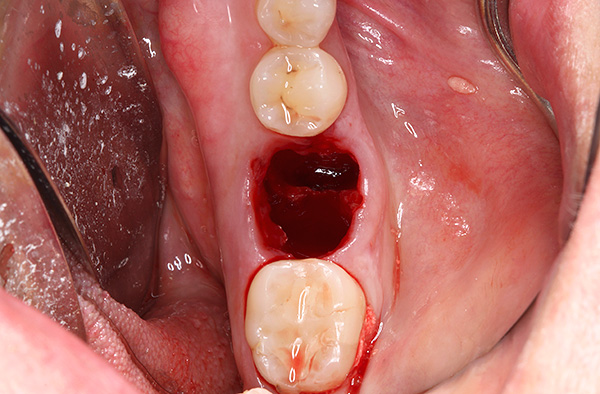

Como o cisto ou granuloma é removido?

Ao remover, o cisto é quase sempre evacuado junto com a raiz do dente, mas também acontece que ele se afasta do ápice da raiz, ou mesmo o ápice da raiz se rompe. Quando o cisto é removido, o dentista-cirurgião raspa a cavidade com uma colher de curetagem ou uma espátula. No caso de quebrar a raiz, ela pode ser removida com elevadores, uma colher de cureta ou cortando com uma broca, seguida de sutura da ferida.